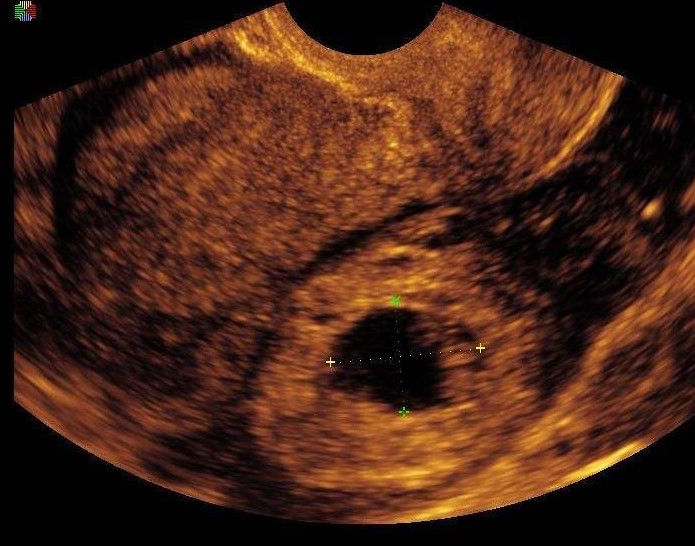

- 超声检查

宫外孕最准确的诊断是超声, 当看到附件区有孕囊,里面有卵黄囊和胚芽,就能确诊 。但是,很多时候孕妈的表现没有那么典型,验尿或是验血发现怀孕后,在附件区发现肿块,这时要高度怀疑宫外孕。

宫外孕有一个“狡猾“”的表现,很迷惑人,20%的宫外孕在宫腔内有“假孕囊”,很像宫内孕的表现,但是里面没有卵黄囊和胚芽,这个是宫腔积液或者积血。